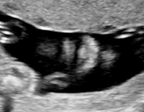

We demonstrate the practical applicability of our method on a challenging medical application, the classification of standardized fetal ultrasound (US) views during prenatal screening. In many countries, US imaging is clinical routine for prenatal health care. The classification of standardized views is important for a consistent, cross-institutional identification of possible abnormalities [47]. Early detection of pathological development can inform following treatment and delivery options [55, 25]. DNNs have shown promising performance to support this task [2]. However, ultrasound images are often hard to interpreted [40]. Anatomical structures have inconsistent appearance [2] and contain different orientations and shapes of anatomical landmarks [1]. Labeled training data is often insufficient as annotating medical images requires significant expertise and is prohibitively expensive in both time and labor. Manifestation of acoustic shadows [17, 44] as shown in Fig. 2(a) as well as different imaging devices as shown in Fig. 2(b) can lead to a domain shift problem for vanilla DNN classifiers. Exploring domain adaptation in fetal US enables DNN classifiers to be effectively utilized on a wider range, which supports identification of abnormalities from varying data sources. This can benefit prenatal healthcare.

The fetal US dataset consists of 2D fetal US images sampled from 2694 2D US examinations with gestational ages between weeks (iFIND Project 555http://www.ifindproject.com/ ). Eight different US systems of identical make and model (GE Voluson E8) were used for the acquisitions to eliminate as many unknown image acquisition parameters as possible. Six different anatomical standard plane locations have been selected by an experienced sonographer, including Four Chamber View (4CH), Abdominal, Femur, Lips, Left Ventricular Outflow Tract (LVOT) and Right Ventricular Outflow Tract (RVOT). The images have additionally been classified by an expert observer as shadow-containing or shadow-free. In this experiment, the source domain contains shadow-free images (see Fig. 2 (b) SF) while the target domain has shadow-containing images from less favorable imaging conditions (see Fig. 2 (b) SC). Training data consists of all six standard planes from the source domain as well as Abdominal, LVOT and RVOT from the target domain. We aim to separate anatomical features (categorical features) and shadow artifacts features (domain features) to obtain generalized anatomical features for achieving high performance of standard plane classification on (4CH, Femur and Lips from target domain). Here, contains 4CH, Abdominal, Femur, Lips, LVOT and RVOT from the source domain and contains Abdominal, LVOT and RVOT from the target domain. Hyper-parameters to in Eq. 11 are for the proposed MIDNet model and is additionally for MIDNet+.